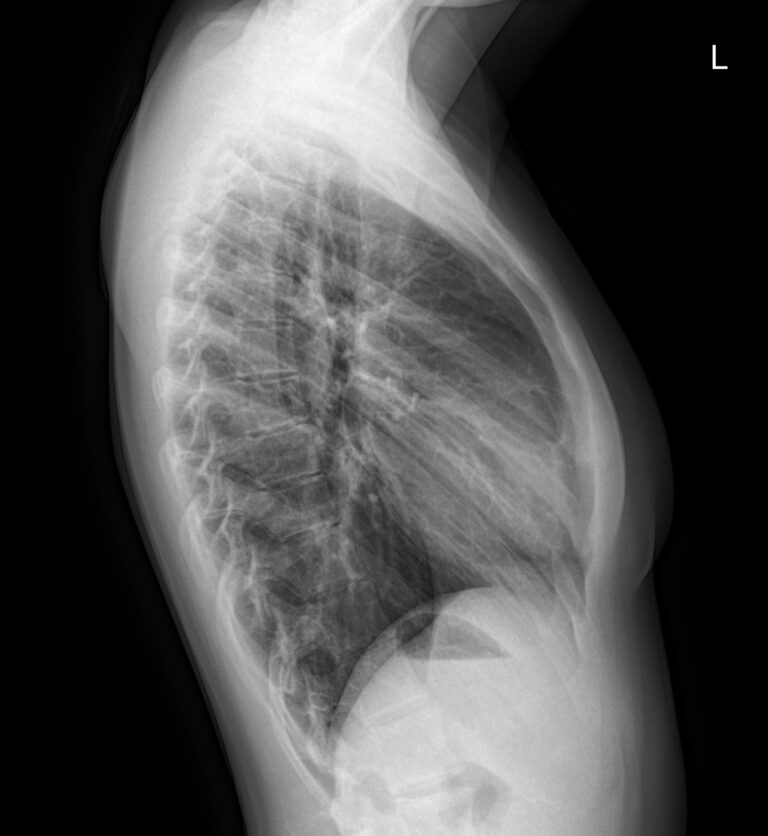

Снимок грудной клетки используют, чтобы получить изображение расположенных здесь органов: легких и дыхательных путей, контуров сердца с сосудами, а также позвоночника и костей. Обычно для диагноза достаточно одного снимка ― в прямой проекции, когда лучи идут сзади наперед. Иногда врач назначает снимок в боковой проекции, то есть слева или справа. Это необходимо, если требуется более точно определить сегмент поражения или достоверно исключить патологический процесс. Крайне редко требуются косые проекции, но они тоже бывают.

• Для прямой или задне-передней проекции необходимо плотно прижаться грудью и плечами к пластине, руки упереть в бока или взяться за специальные поручни;

• Если дополнительно требуется боковая проекция, пациент встает и прижимается боком, подняв руки над головой.